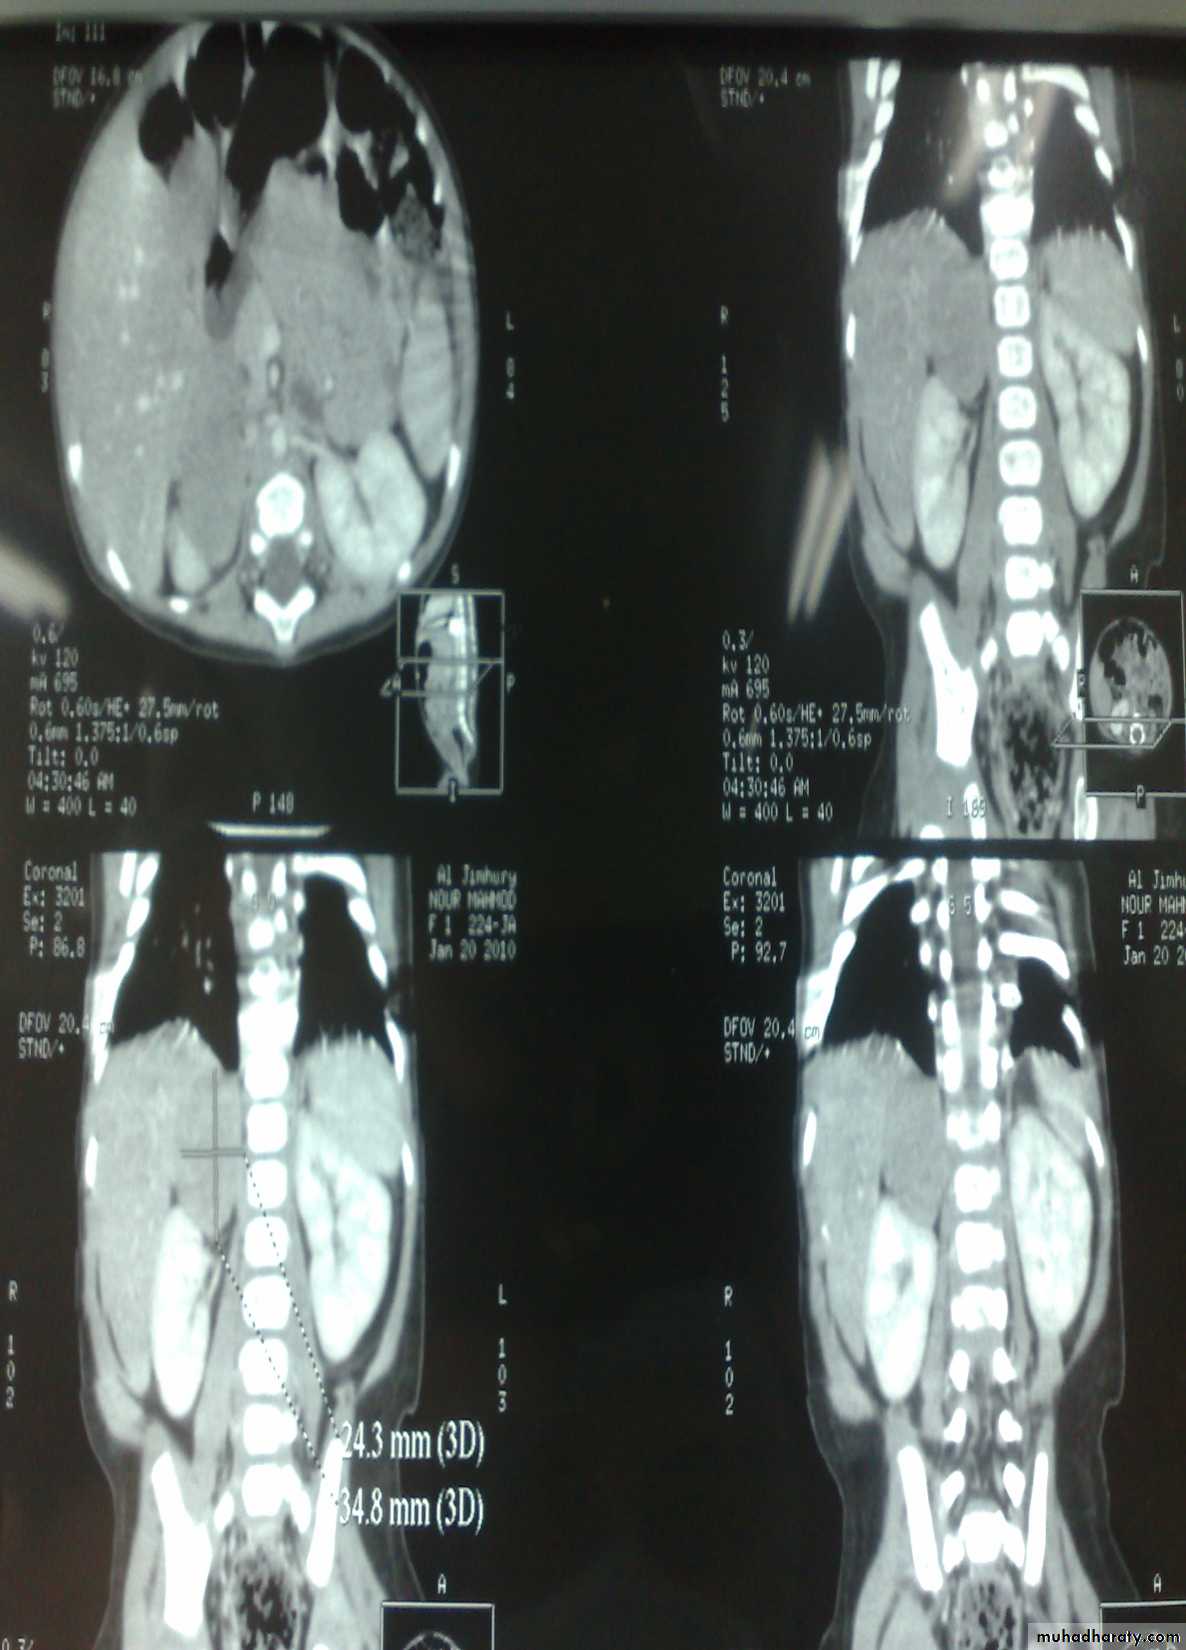

The Child with an Abdominal Mass

Pediatric surgery practical